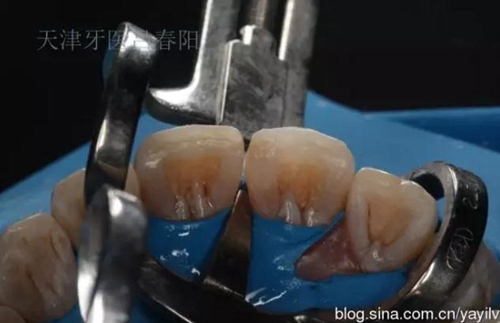

前牙齲洞的美學(xué)樹脂充填修復(fù) 科貿(mào)嘉友收錄

發(fā)一個最近完成的病例吧,雖然齲洞不大,但是挺好玩的,我自己認為。